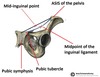

Mid point of inguinal ligament

Halfway between ASIS and tubercle

Which structure associated with mid point of inguinal ligament

Deep inguinal ring